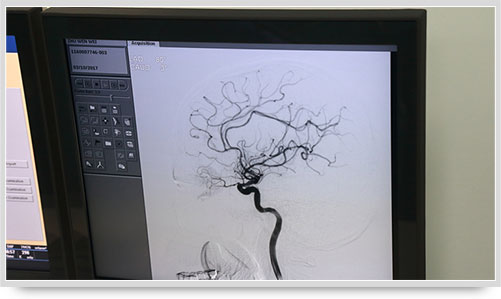

全脑血管造影术(DSA)是运用数字减影技术下进行的全脑血管摄片,因此又称数字减影血管造影。技术上一般采用局部麻醉,右侧股动脉穿刺、置管,再将一根造影管通过腹主动脉、主动脉弓,选择性进入左右颈内动脉和椎动脉后,分别造影,发现病灶后还应行三维血管造影。造影图像较以往所用的常规脑血管造影所显示的图像,更清晰和直观,一些精细的血管结构亦能显示出来,是目前国际上公认的血管性疾病诊断的“金标准”。

弓上造影、超选到颈内动脉、椎动脉......在数字减影技术下,注入显影剂后,导管经患者右侧股动脉在体内推进,由于股动脉离脑血管距离较远,中间“路程复杂”,对施术医生的要求非常之高。

同时,手术台前的液晶显示仪屏幕上清晰地现显出导管的路径,在李主任的操作下准确到达指定检查部位,各条血管的“庐山真面目”清晰可见。